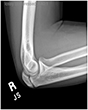

Olecranon Stress Fracture

The patient is an elite baseball pitcher who felt progressive pain in the posterior aspect of his elbow during fall ball. He presented with a stiff shoulder, a diminished arc of motion, and deficiencies in his core musculature. X-rays demonstrated an olecranon stress fracture (far right xray – red arrow). He was shut down from throwing and began to work in physical therapy for his range of motion deficiencies. At two months, the stress fracture showed progression of healing (middle image). By three months, his olecranon stress fracture had healed and he was allowed to begin an interval throwing program (far left xray – red arrow). He returned to pitching at an elite level.